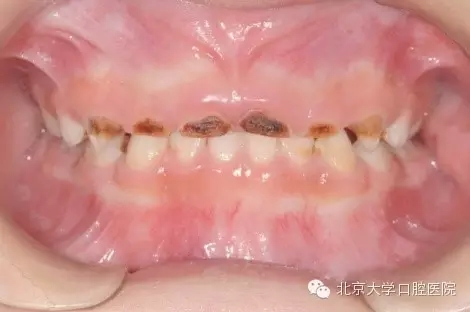

全身麻醉下兒童牙齒治療是一項針對在口腔醫(yī)學(xué)臨床工作中難于對牙科恐懼癥患兒、低齡及智障兒童實施常規(guī)口腔診療的特色技術(shù)項目。從1999年開始,北京大學(xué)口腔醫(yī)院兒童口腔科和麻醉科相互協(xié)作在國內(nèi)率先開展該治療技術(shù)。近二十年來,北大口腔醫(yī)院兒科已建成了設(shè)備先進的全麻治療室,累計完成全麻下牙齒治療患者數(shù)千例,使該技術(shù)成為北大口腔醫(yī)院特色醫(yī)療技術(shù)之一。該治療技術(shù)優(yōu)點是在一次治療中醫(yī)生可以高質(zhì)高效地完成全口所有需進行的治療工作,特別適用于配合能力差,治療需要量大的患兒。

1.webp.jpg